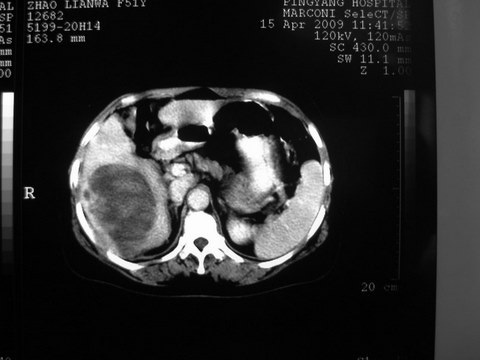

患者 女 51岁 两天前感觉上腹疼,无明显诱因,b超示肝右叶囊实性占位,边缘清楚,其内回声不均匀,ct增强如图,大家看看是什么 ,病人一年前及两月前b超检查只是提示胆囊炎

外院术后,证实肝癌合并出血

特点:1,病灶发展迅速,(2月前正常)[br] 2,囊实性,且并边界清晰光滑,呈右后叶赘生性。囊性区无强化,实性部分较多轻度强化,边界欠清。考虑囊腺癌或囊腺瘤。

出病理 中分化肝细胞癌合并出血